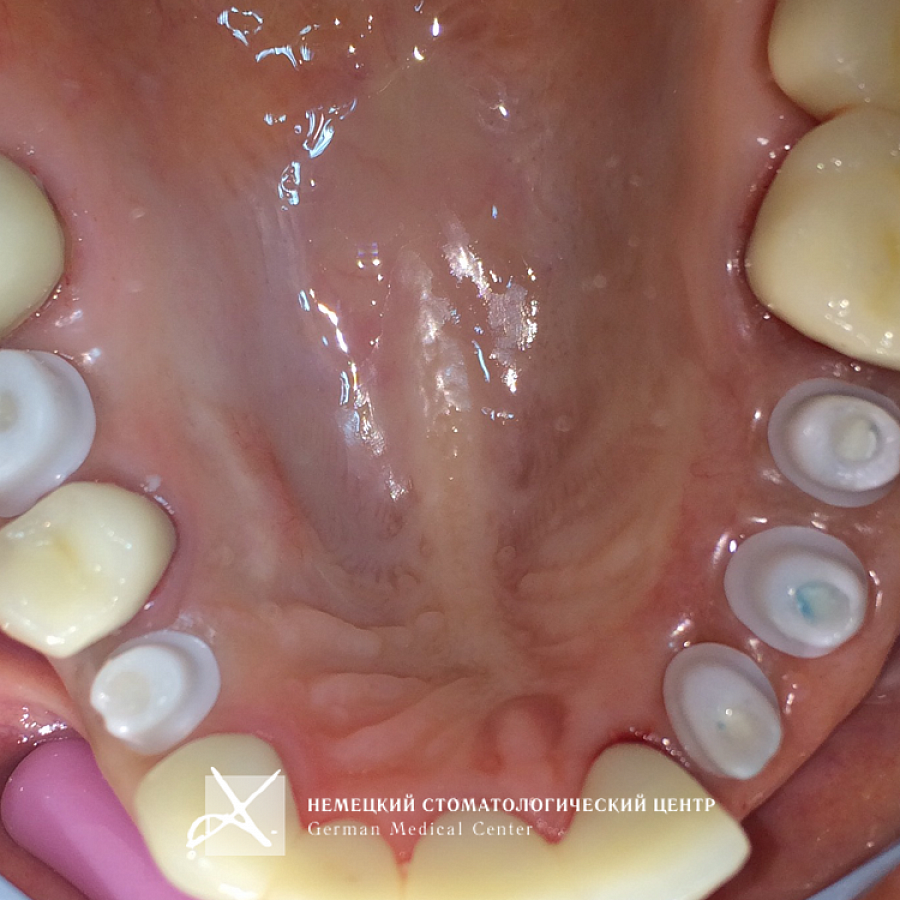

Пациентка обратилась с задачей восстановить целостность зубных рядов.

Пациентке проведено полноценное восстановление зубных рядов конструкциями с опорой на зубы и имплантаты. Коронки и абатменты изготовлены из диоксида циркония. Во время подготовительных мероприятий пациентка пользовалась временными конструкциями.